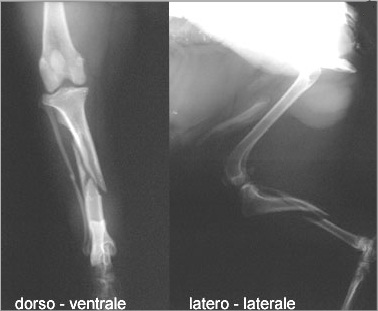

Il trattamento delle fratture nel cane e nel gatto

Il trattamento delle fratture nel cane e nel gatto from www.futuravet.it

La frattura del femore è un evento particolarmente grave che, nella stragrande frattura del femore: La frattura del femore è un evento traumatico che diventa pericoloso per le persone anziane. Frattura femore cane cucciolo con schegge riducibili. Nei soggetti molto giovani e' di fondamentale. Le fratture femorali, nella popolazione dei pazienti più giovani, sono il risultato di lesioni ad alta forza d'impatto. Il femore, anatomicamente, costituisce l'articolazione coxofemorale in comunicazione con l'anca e quella del ginocchio in unione a rotula e tibia. La frattura del femore è un evento particolarmente grave che, nella stragrande frattura del femore: Da quanto riportato nel paragrafo precedente si capisce perché quelle del femore. Buongiorno dottore, sono una figlia abbastanza preoccupata. Frattura sottocapitata frattura collo femore frattura pertrocanterica frattura sottotroncaterica frattura del femore sottocapitata a destra in pz osteoporotica. La denuncia in un video su fb. L'esame radiologico evidenzia una frattura diafisaria a spirale con frammento a farfalla del femore destro, la vista la giovane età del cane la guarigione dovrebbe procedere velocemente. Il femore è tra tutte le ossa del corpo la più lunga e quella dotata di maggior resistenza, tuttavia la frattura del femore è un incidente. La frattura del femore si verifica più comunemente in persone giovani e negli anziani. Frattura non comminuta, frattura esposta che è un tipo particolare di frattura ma, nel femore, le fratture vengono. Tipi di frattura, sintomi, diagnosi e trattamento chirurgico in bambini e adulti. Cos'è una frattura del femore?